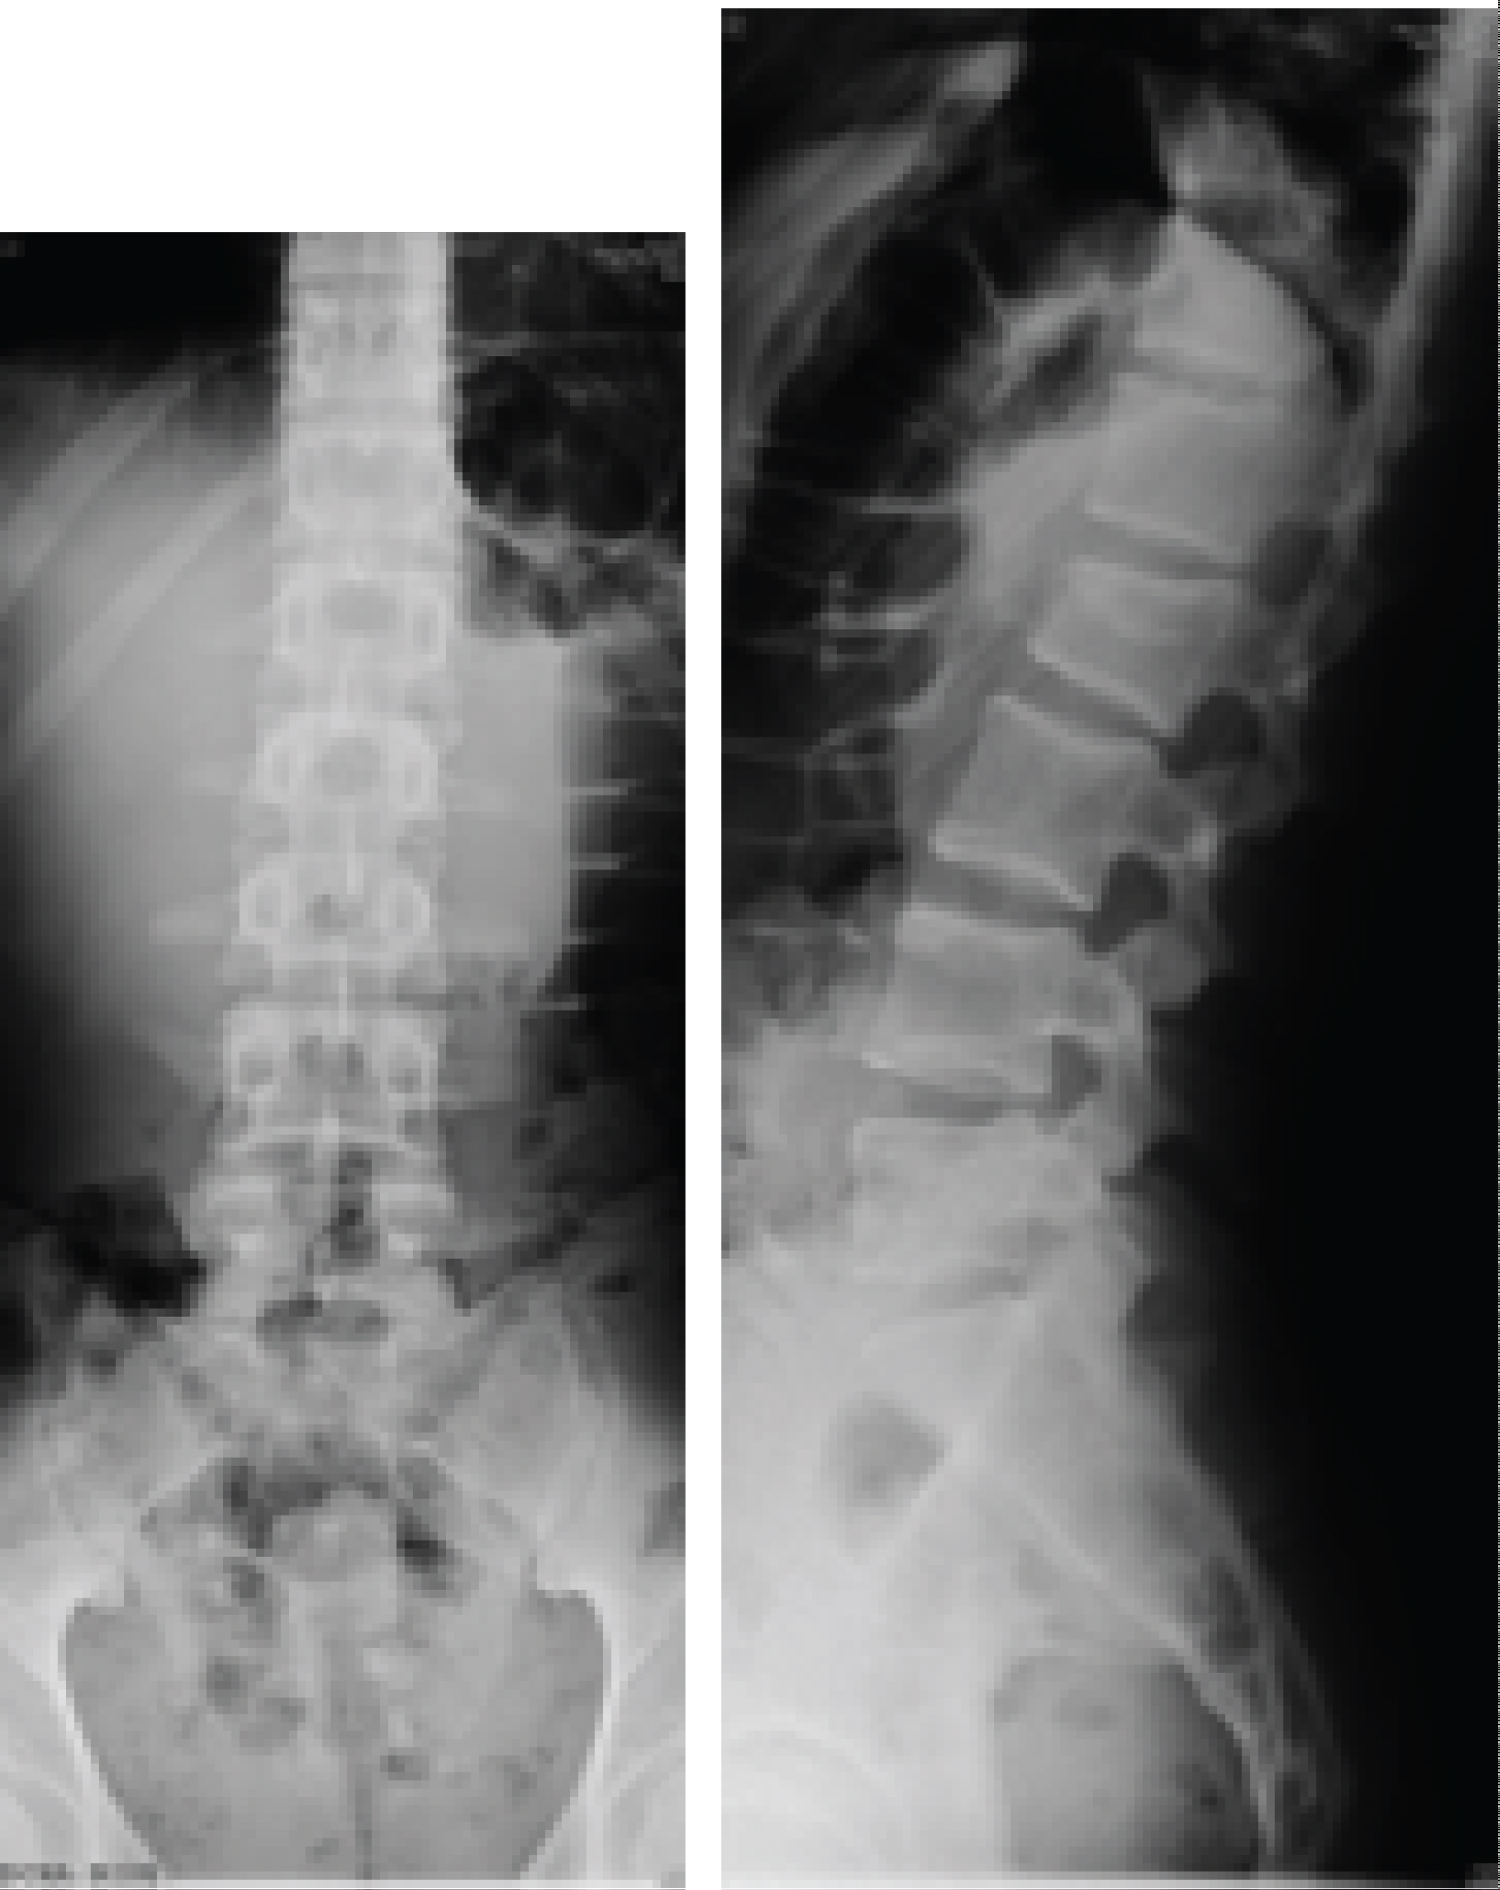

On radiographs and (CT), a simple L2 fracture was observed, which could be classified as AOSpine A1-type fracture with a Farcy kyphosis less than 16o and therefore make us think about the conservative treatment with corset (Figure 1 and Figure 2).

Figure 1: (a) Sagittal rx (b) Frontal rx images demonstrates a fracture at L2 (A1), (AO classification). View Figure 1